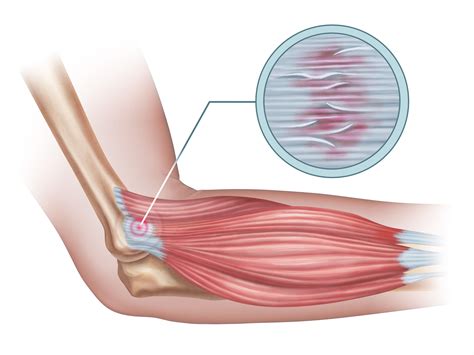

Understanding Tendinosis

Tendinosis, on the other hand, is a degenerative condition that affects the tendons. Unlike tendinitis, tendinosis does not involve inflammation. Instead, it is characterized by the breakdown of collagen fibers within the tendon, leading to weakened and damaged tissue. This condition is often the result of chronic overuse or repetitive stress on the tendon.